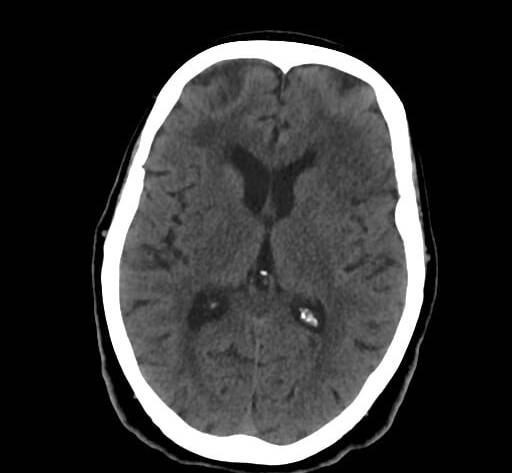

Beyin Tomografisi Nedir?

Beyin tomografisi (Beyin BT), beynin kesitsel görüntülerini elde etmek için kullanılan hızlı ve etkili bir görüntüleme yöntemidir. Özellikle acil durumlarda tercih edilir.

Beyin Tomografisi Ne Gösterir?

Beyin Kanaması

Acil durumlarda en hızlı tanı koyan yöntemdir.

İnme

Erken dönemde hayati bilgi verir.

Tümörler

Kitlelerin varlığı tespit…